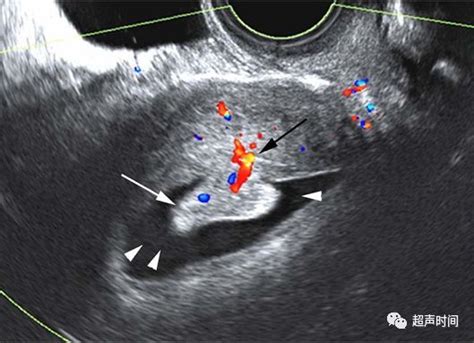

子宫内膜占位

子宫内膜增厚,宫腔占位

宫腔占位是什么意思

如液体(盆腔积液、感染化脓)、病变(肿瘤、囊肿、增生、血液凝集块、人流后未曾刮净而遗留残体)。就是宫腔内有了不该有的物质。

占位就是长了个东西,非正常的。宫腔占位 息肉待排,即:有可能是宫腔息肉;宫颈液性占位 积液,已经说得很明白:宫颈积液。需要手术